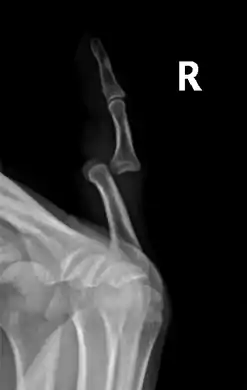

خلع في سبابة اليد اليسرى